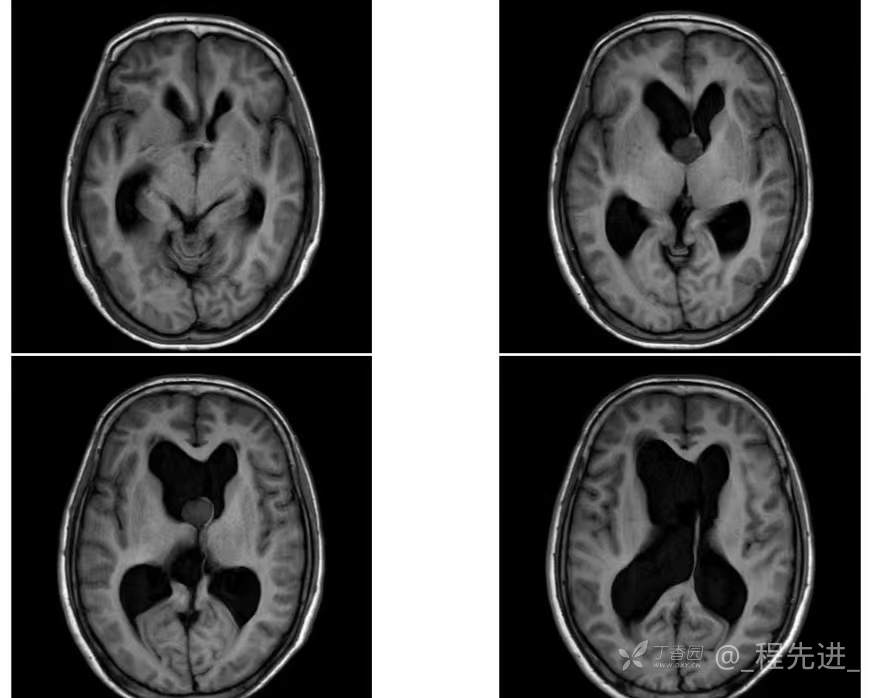

患者性别:女

患者年龄:55岁

简要病史:头痛头晕4年余,无明显诱因,10余年前因“输卵管破裂大出血”手术治疗

辅助检查:实验室检查无特殊